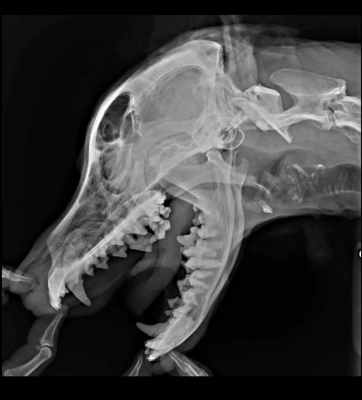

06.03 - посещение хирурга-стоматолога.

Результаты посещения ошеломляюще плохие:

5. рентген челюсти.